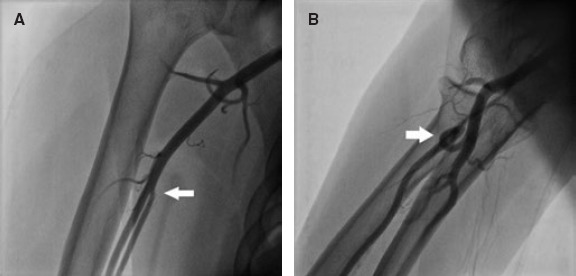

Results: Our study population included 288 men (67.4%) and 139 women (32.6%). The mean age was 61.9 ± 11.1 years. RAO occurred in 48 patients (11.24%), and spontaneous recanalization was observed within 3 months in 15 patients (32.6%). On multivariate analysis, independent predictors of RAO were younger age (OR, 0.642; 95%CI, 0.480-0.858; P = .031), low periprocedural systolic blood pressure (OR, 0.598; 95%CI, 0.415-0.862; P = .007), a small radial diameter (OR, 0.371; 95%CI, 0.323-0.618; P = .031), insufficient anticoagulation (OR, 0.287; 95%CI, 0.163-0.505; P < .001), occlusive hemostasis (OR, 0.128; 95%CI, 0.047-0.353; P < .001), and long duration of hemostasis. The overall incidence of RA anatomic variations was 14.8% (n = 63). Among these, 40 patients (63.5%) had a high radial origin, 18 (28.6%) had extreme RA tortuosity, and 5 (7.9%) had a complete radioulnar loop.

Abstract Image